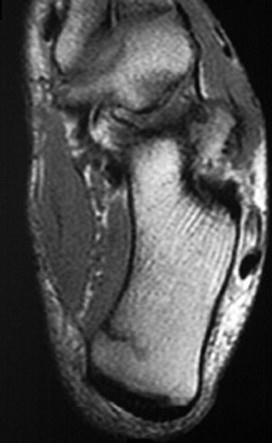

女,48岁,長跑运动员,左跟骨部痛,结合图像,最可能的诊断是 ( )A、左踝关节退行性变B、应力性骨折C、左跟骨骨髄炎D、结核...

问题 女,48岁,長跑运动员,左跟骨部痛,结合图像,最可能的诊断是 ( )

选项 A、左踝关节退行性变 B、应力性骨折 C、左跟骨骨髄炎 D、结核 E、未见异常

答案 B